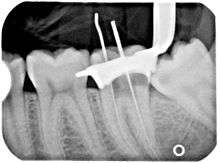

Another common complication of root canal therapy is when the entire length of the root canal is not completely cleaned out and filled (obturated) with root canal filling material (usually gutta percha). The X-ray in the right margin below shows two adjacent teeth that had received bad root canal therapy. The root canal filling material (3, 4 & 10) does not extend to the end of the tooth roots (5, 6 & 11). The dark circles at the bottom of the tooth roots (7 & 8) indicated infection in the surrounding bone. Recommended treatment is either to redo the root canal therapy if possible or extract the tooth and place dental implant(s). [31]